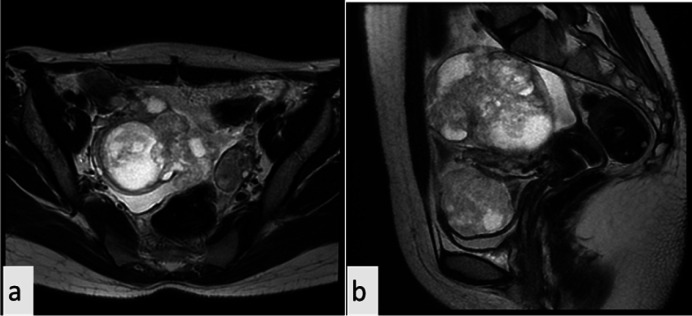

Wolffian adnexal tumors (FATWOs) originate from the mesonephric duct remnants. FATWOs are extremely rare and 100 incidental FATWOs have been reported in the English literature as of now. Most FATWOs have low potential for malignancy but aggressive behavior including recurrence and metastasis have been described in few cases; There is no standard protocol for optimal treatment of FATWOs. The case described here is a 35-year-old female who presented with a right-side ovarian mass via abdominal ultrasound. She had a history of left salpingo-oophorectomy due to an abdominal mass, which both histopathologic and immunohistochemical study's findings were consistent with Wolffian tumor. Later, she underwent total abdominal hysterectomy with tumor debulking because of the probable malignant behavior of the tumor. FATWO has a heterogeneous histologic pattern which may make its diagnosis challenging. No specific immunohistochemical markers have yet been recognized for FATWO and pathogenesis or molecular alterations are not definitive. Therefore, there is no comprehensive recommendation for optimal clinical management of FATWO or its recurrence.